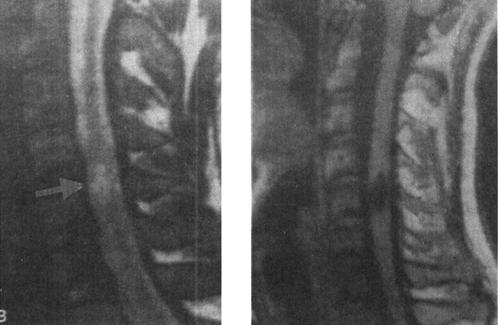

(2)脊髓软化和空洞:脊髓软化在创伤后48h后即可开始,是由于脊髓内出血、水肿引起的炎症性反应和肉芽组织对创伤组织的清除所致,可能同时伴有胶质细胞的增生和吞噬细胞功能的增强使脊髓脂质崩解、软化和液化,并被吞噬细胞吞噬和转移,最终形成脊髓软化和空洞形成。MRI可显示这种病理改变。脊髓软化灶在T1WI表现为低信号,在T2WI为高信号,增强扫描无强化。脊髓空洞在T1WI和T2WI信号等同于脑脊液信号,而边缘更加清晰(图7-19)。脊髓软化和空洞是神经系统症状恶化的主要原因。脊髓空洞引流是治疗的重要手段,因而正确的诊断和定位十分重要。大约9%~20%的脊髓损伤病人可出现脊髓空洞症。

图7-19 脊髓创伤后脊髓软化:MRI、T1WI和T2WI矢状面显示C5水平颈髓内可见一长条状异常信号影,T1W低信号,T2W高信号,类似脑脊液信号,为创伤后软化灶